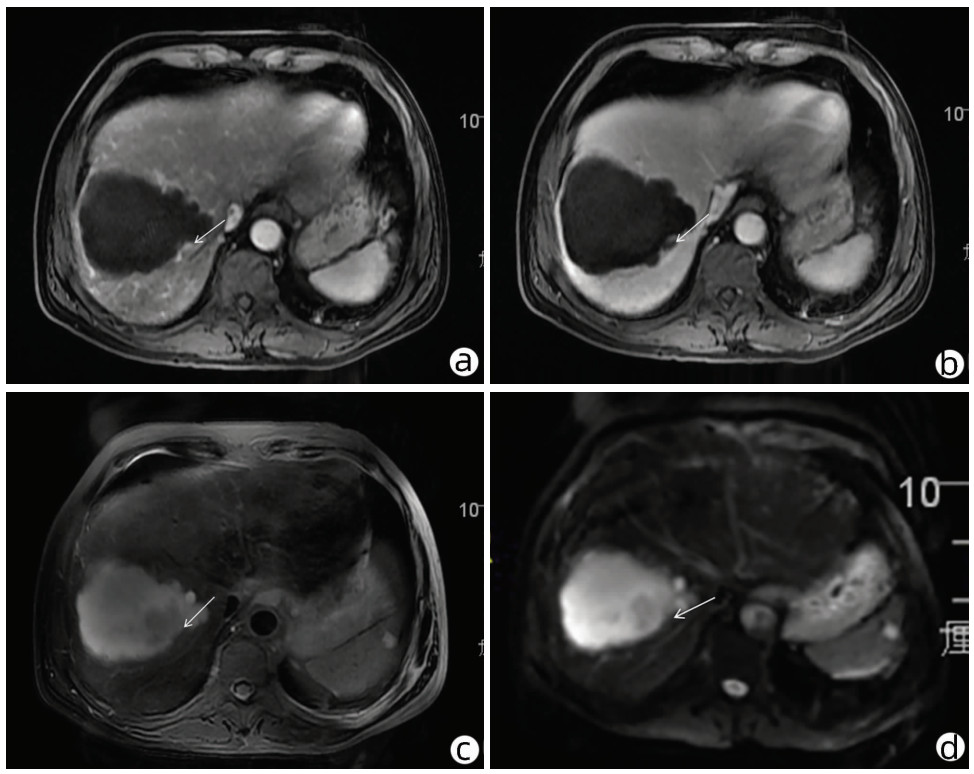

作者贡献声明:雷进负责资料分析,撰写论文;张林枝、陈博文负责提出具体修改意见并进行修改;左石、陆荫英负责拟定撰写思路,指导文章写作并最终定稿。